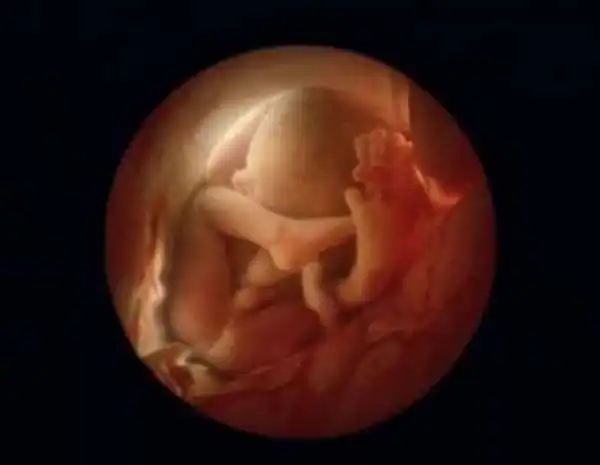

Получить наиболее точные и красочные снимки ему помог цистоскоп- медицинский прибор, с помощью которого осматривают мочевой пузырь изнутри. Нильсон прикрепил к нему камеру и световод и сделал тысячи снимков жизни малыша внутри матки.

10 недель. Малыш уже использует руки для изучения окрестностей

16 недель